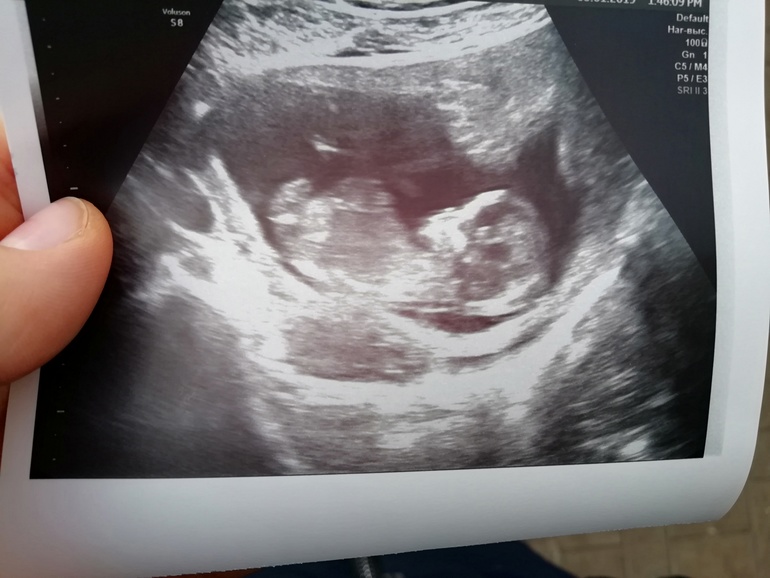

Добрый день 😍вышла с узи, и хочется летать, пархать, кричать и все от радости 🙈когда начали показывать эти ручки, ножки, животик, головку, я тюфяк, давай слезы подбирать... Спросила кто, сказали похоже на девочку.. Когда-то ниже писала, что хочу пацана, так вот сегодня после УЗИ поняла, что абсолютно все равно, я безумно рада и девочке и мальчику... Она просто чудесная, во время узи мы сладко спали сложив ручки на животике 🙈😍❤️меня распирает от счастья и любви к ней 😭😍 Узистке очень пришлось постараться поймать, матка была в тонусе, как она пояснила то ли это вы мамочка так перенервничали то ли это джинсы узкие, которые посоветовала сменить, но с джинсами конечно я сегодня вообще надурила, все из-за своей рассеяности.. А так сказали все у нас хорошо, до 9 январь кровь сдайте)